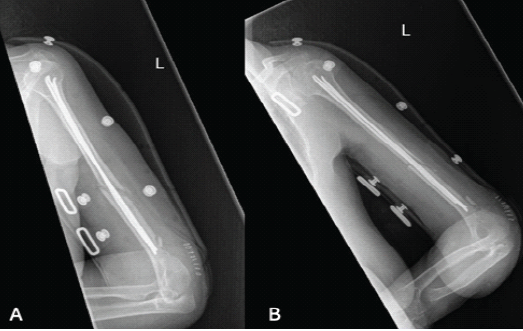

The patient had an uneventful post-operative course and was discharged on day 1 postoperatively after controlling pain and ensuring an intact neurovascular function with immediate range of motion exercises. The patient was in a splint for 2 weeks and then was seen in the office. The incision was well healed, and the patient remained neurovascularly intact. She was NWB for 6 weeks after surgery and advanced to progressive weight bearing as tolerated (Fig. 3).

Figure 3: (a) Anterior-posterior X-ray of the humerus 2 weeks postoperatively, (b) Lateral X-ray of the humerus 2 weeks postoperatively.